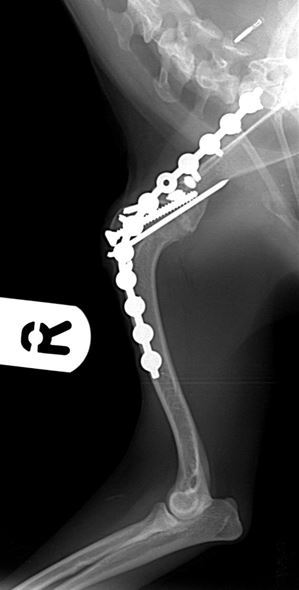

Radiographs taken 8 weeks after surgery showed good progression of arthrodesis and no evidence of any implant associated problems.

Figures 3 & 4. Mediolateral and caudocranial radiographs of the arthrodesed shoulder 8 weeks after surgery, showing good progression of arthrodesis and good alignment of the shoulder and elbow joints with the shoulder at a standing angle.